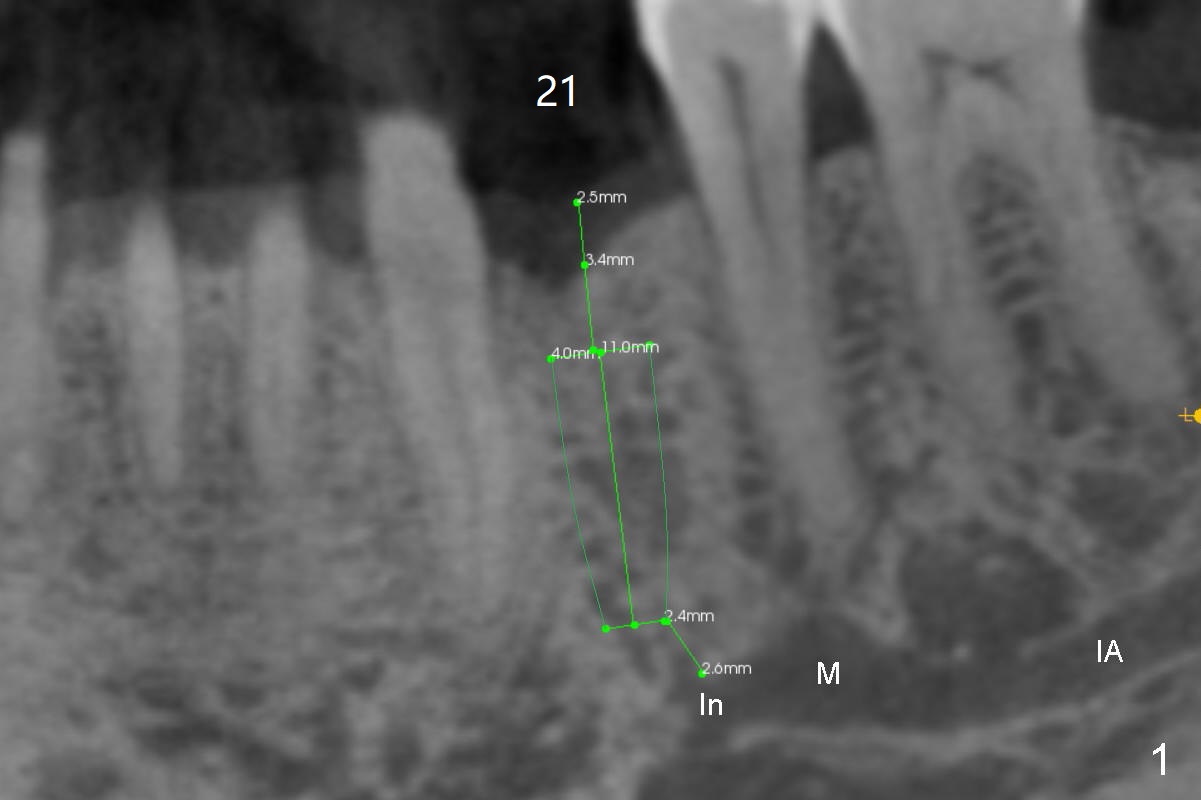

A 75-year-old man requests implant placement at #21 several years after traumatic extraction (Fig.1) with the narrow ridge (Fig.2). After ridge reduction ~ 3.5 mm (Fig.1,3), a 3.5x11 mm implant will be placed to avoid the Incisive canal (In in Fig.1,4) and the Mental Loop (M). In fact the patient agrees to have guided surgery and then changes mind.